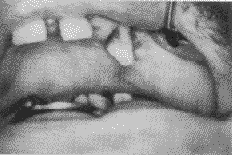

例1 男,58岁。左侧硬腭粘膜鳞状细胞癌T2N0M0,硬腭骨质部分受侵,上唇及鼻侧切开入路,将左半侧硬腭切除。缺损约5 cm×6 cm大小。同侧头皮冠状切口,切取7 cm×12 cm大小帽状腱膜瓣,从颧弓深面折入口腔,修复硬腭缺损,腱膜瓣全部存活(图2)。术后第3天即经口进食。术后1年复查,帽状腱膜瓣收缩约30%,表面已粘膜化,粘膜下可见较多的毛细血管(图3),患者未配戴人工腭托,发音和进食正常,无并发症。

图2 帽状腱膜瓣修复左侧硬腭缺损。术后第2周外观,表面有肉芽组织生长

图3 与图2为同一病例。术后1年外观,帽状腱膜瓣收缩大约30%,表面已粘膜化